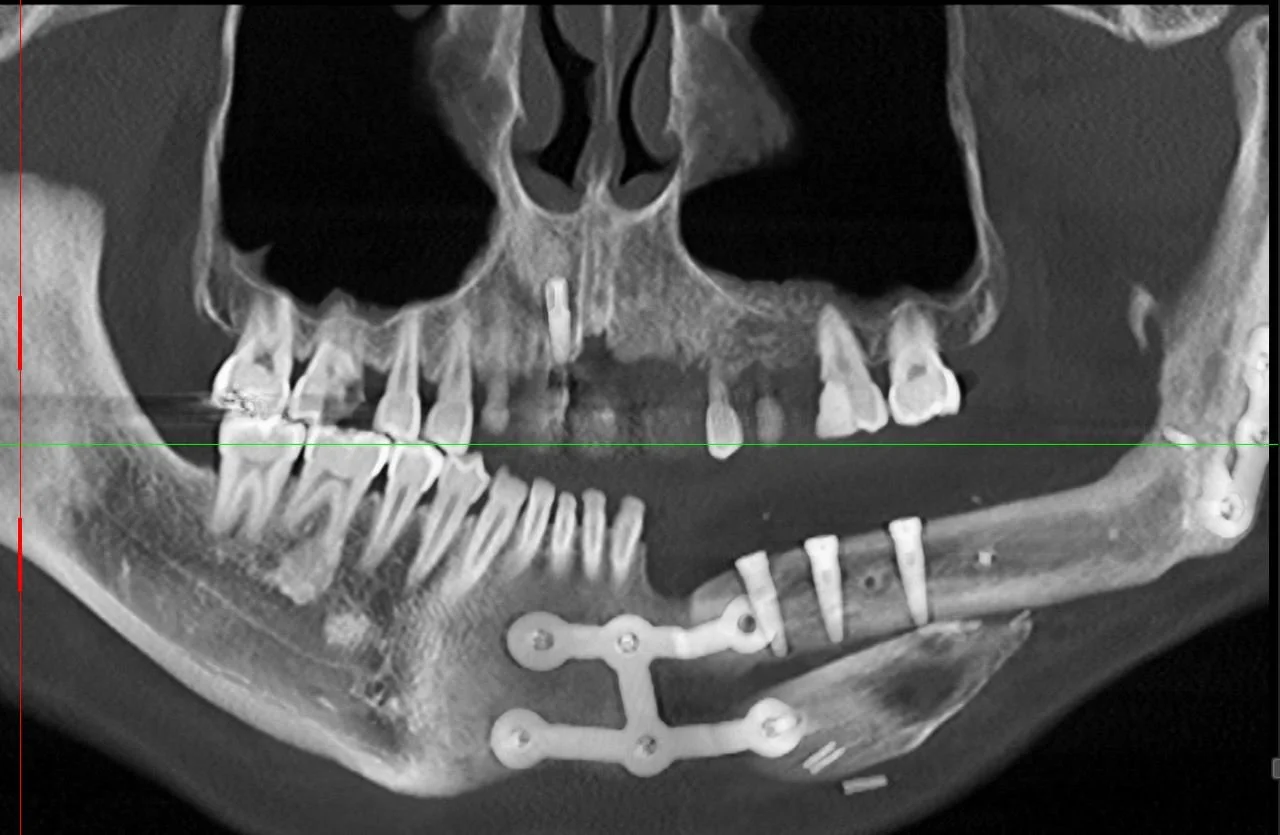

The patient was referred to me at Lismore in 2021 to replace the missing teeth with a fixed prosthesis involving an implant bridge. I designed the bridge on an OPG radiograph and issued instructions to my ceramist technician to fabricate a diagnostic wax up of the future teeth .

-

A surgical guiding device was fabricated with radiographic markers (vertical pink GP points) placed in the centre of the teeth to demarcate the future centroid position of the implant fixtures .

The guiding device was designed to bite optimally on the upper opposing teeth to duplicate where the future implant teeth would bite. Please note the soft tissue calf graft at this stage of treatment.

The surgical guiding device was given to the surgeon and his technical team to verify the position of my diagnostic teeth radiographic markers relative to the available bone to confirm the suitability for implant placement .

This OPG radiograph illustrates the completed 3 implant fixture and note that two of the metal splints had to be removed for implant placement. Note there was insufficient bone in the lower left canine region to place an implant which necessitated the designing of a cantilevered bridge tooth